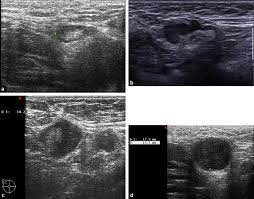

Breast ultrasound images are seen from superficial (skin) to deep (chest wall muscle) over a segment of tissue. Other ultrasound findings that suggest breast cancer include: Looks larger, thicker or heavier. Other ultrasound findings that suggest breast cancer include: Presenting radiologic appearance of breast dcis microcalcifications at breast cancer screening we can see from the chart above that overall, the most commonly occuring mammographic indication of dcis are the crushed stone microcalcifications. This can make it harder for your radiologist to spot signs of breast cancer, since dense tissue and tumors both look white in mammogram images. While it may look like a fuzzy, spotty television screen with different shades of grey to a patient, the ultrasound technician and the radiologist use these images to diagnose masses and tumors. Any area that does not look like normal tissue is a possible cause for concern.

There is a slight increase in the density in the right breast compared with the left. But radiologists can still see signs of cancer. Looks larger, thicker or heavier. Rather, the right breast is seen as smaller than the left breast. The breast tissue kind of looks like waves on the ocean. Inflammatory breast cancer pictures and symptoms. Is tender, aches or feels painful. It is an infiltrating, malignant and abnormal proliferation of neoplastic cells in the breast tissues. The sound waves pass through the breast and bounce back or echo from various tissues to form a picture of the internal structures of the breast. Mri has a wide spectrum of findings for fat necrosis and the appearance is the result of the amount of the inflammatory reaction, the amount of. My doctor found a lump in my breast during my yearly mammogram and then brought in an ultrasound technician to follow up with an ultrasound for a closer look. Finding breast lumps and seeing change in the size and shape. Breast ultrasound images are seen from superficial (skin) to deep (chest wall muscle) over a segment of tissue.

Ultrasound does not use or. Inflammatory breast cancer pictures and symptoms. As the machine is moved over an area of the breast, the device sends sound waves into the tissue, and it shows an image based on how quickly those waves bounce back to it. Both the mammogram and ultrasound looked fuzzy and gray on the screen and i have no idea. Ultrasound images are black and white, showing a small portion of the breast at a time.